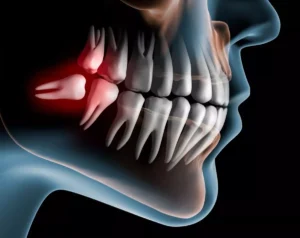

Bölcsességfogak: Nyirokcsomó duzzanat léphet fel egy előtörésben akadályozott begyulladt bölcsességfog, az impaktált bölcsességfog növekedése esetén, vagy ha a bölcsességfog rosszul nő és a szomszédjába ütközik. Jelezhetnek a nyirokcsomók azoknál is, amelyek nem bújnak ki teljesen és az íny által részben fedve maradnak és gyulladt tasak képződik körülöttük.

A fogászati eredetű okok közül a legtöbbször a bölcsességfog kinövés során tapasztalható állcsont nyirokcsomó duzzanat. A legtöbb problémát általában a bölcsességfog gyulladás okozza.

Problémás lehet az előbújásuk, és nehéz a tisztíthatóságuk. Gyakran tasak vagy ciszta képződik körülöttük. Könnyen elromlanak, s mivel nehezen hozzáférhető az orvos számára, így például egy több lépéses bölcsességfog gyökérkezelés is csak ritkán kivitelezhető.

- Ha a bölcsesség fog akadályozva van az előtörésben, akkor bölcsességfog műtét vár rá.